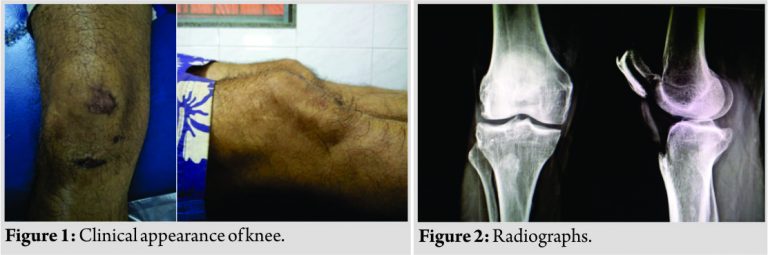

A 54-year-old man attended the emergency department of the hospital with a painful locking of the right knee. He was trying to attain a kneeling position on the bed when his knee struck on the edge of the bed. Clinical examination (Fig.1) revealed no palpable gap in the patellar tendon. The superior pole of the patella was projecting anteriorly and there was a prominent dimple below the patella. The patient was not able to perform straight leg raising. Plain radiographs (Fig. 2) confirmed a superior dislocation of the patella, which was manipulated by passing fingers under the prominent surface of patella, lower pole of patella was pushed posteriorly, and upper pole was pushed distally, gently flexing and then extending the knee which provided immediate pain relief. This procedure was done under the effect of intramuscular analgesia. The knee was then immobilized in a posterior long knee brace for three weeks. After three weeks, patient was active with pain-free range of movements and a stable right knee.